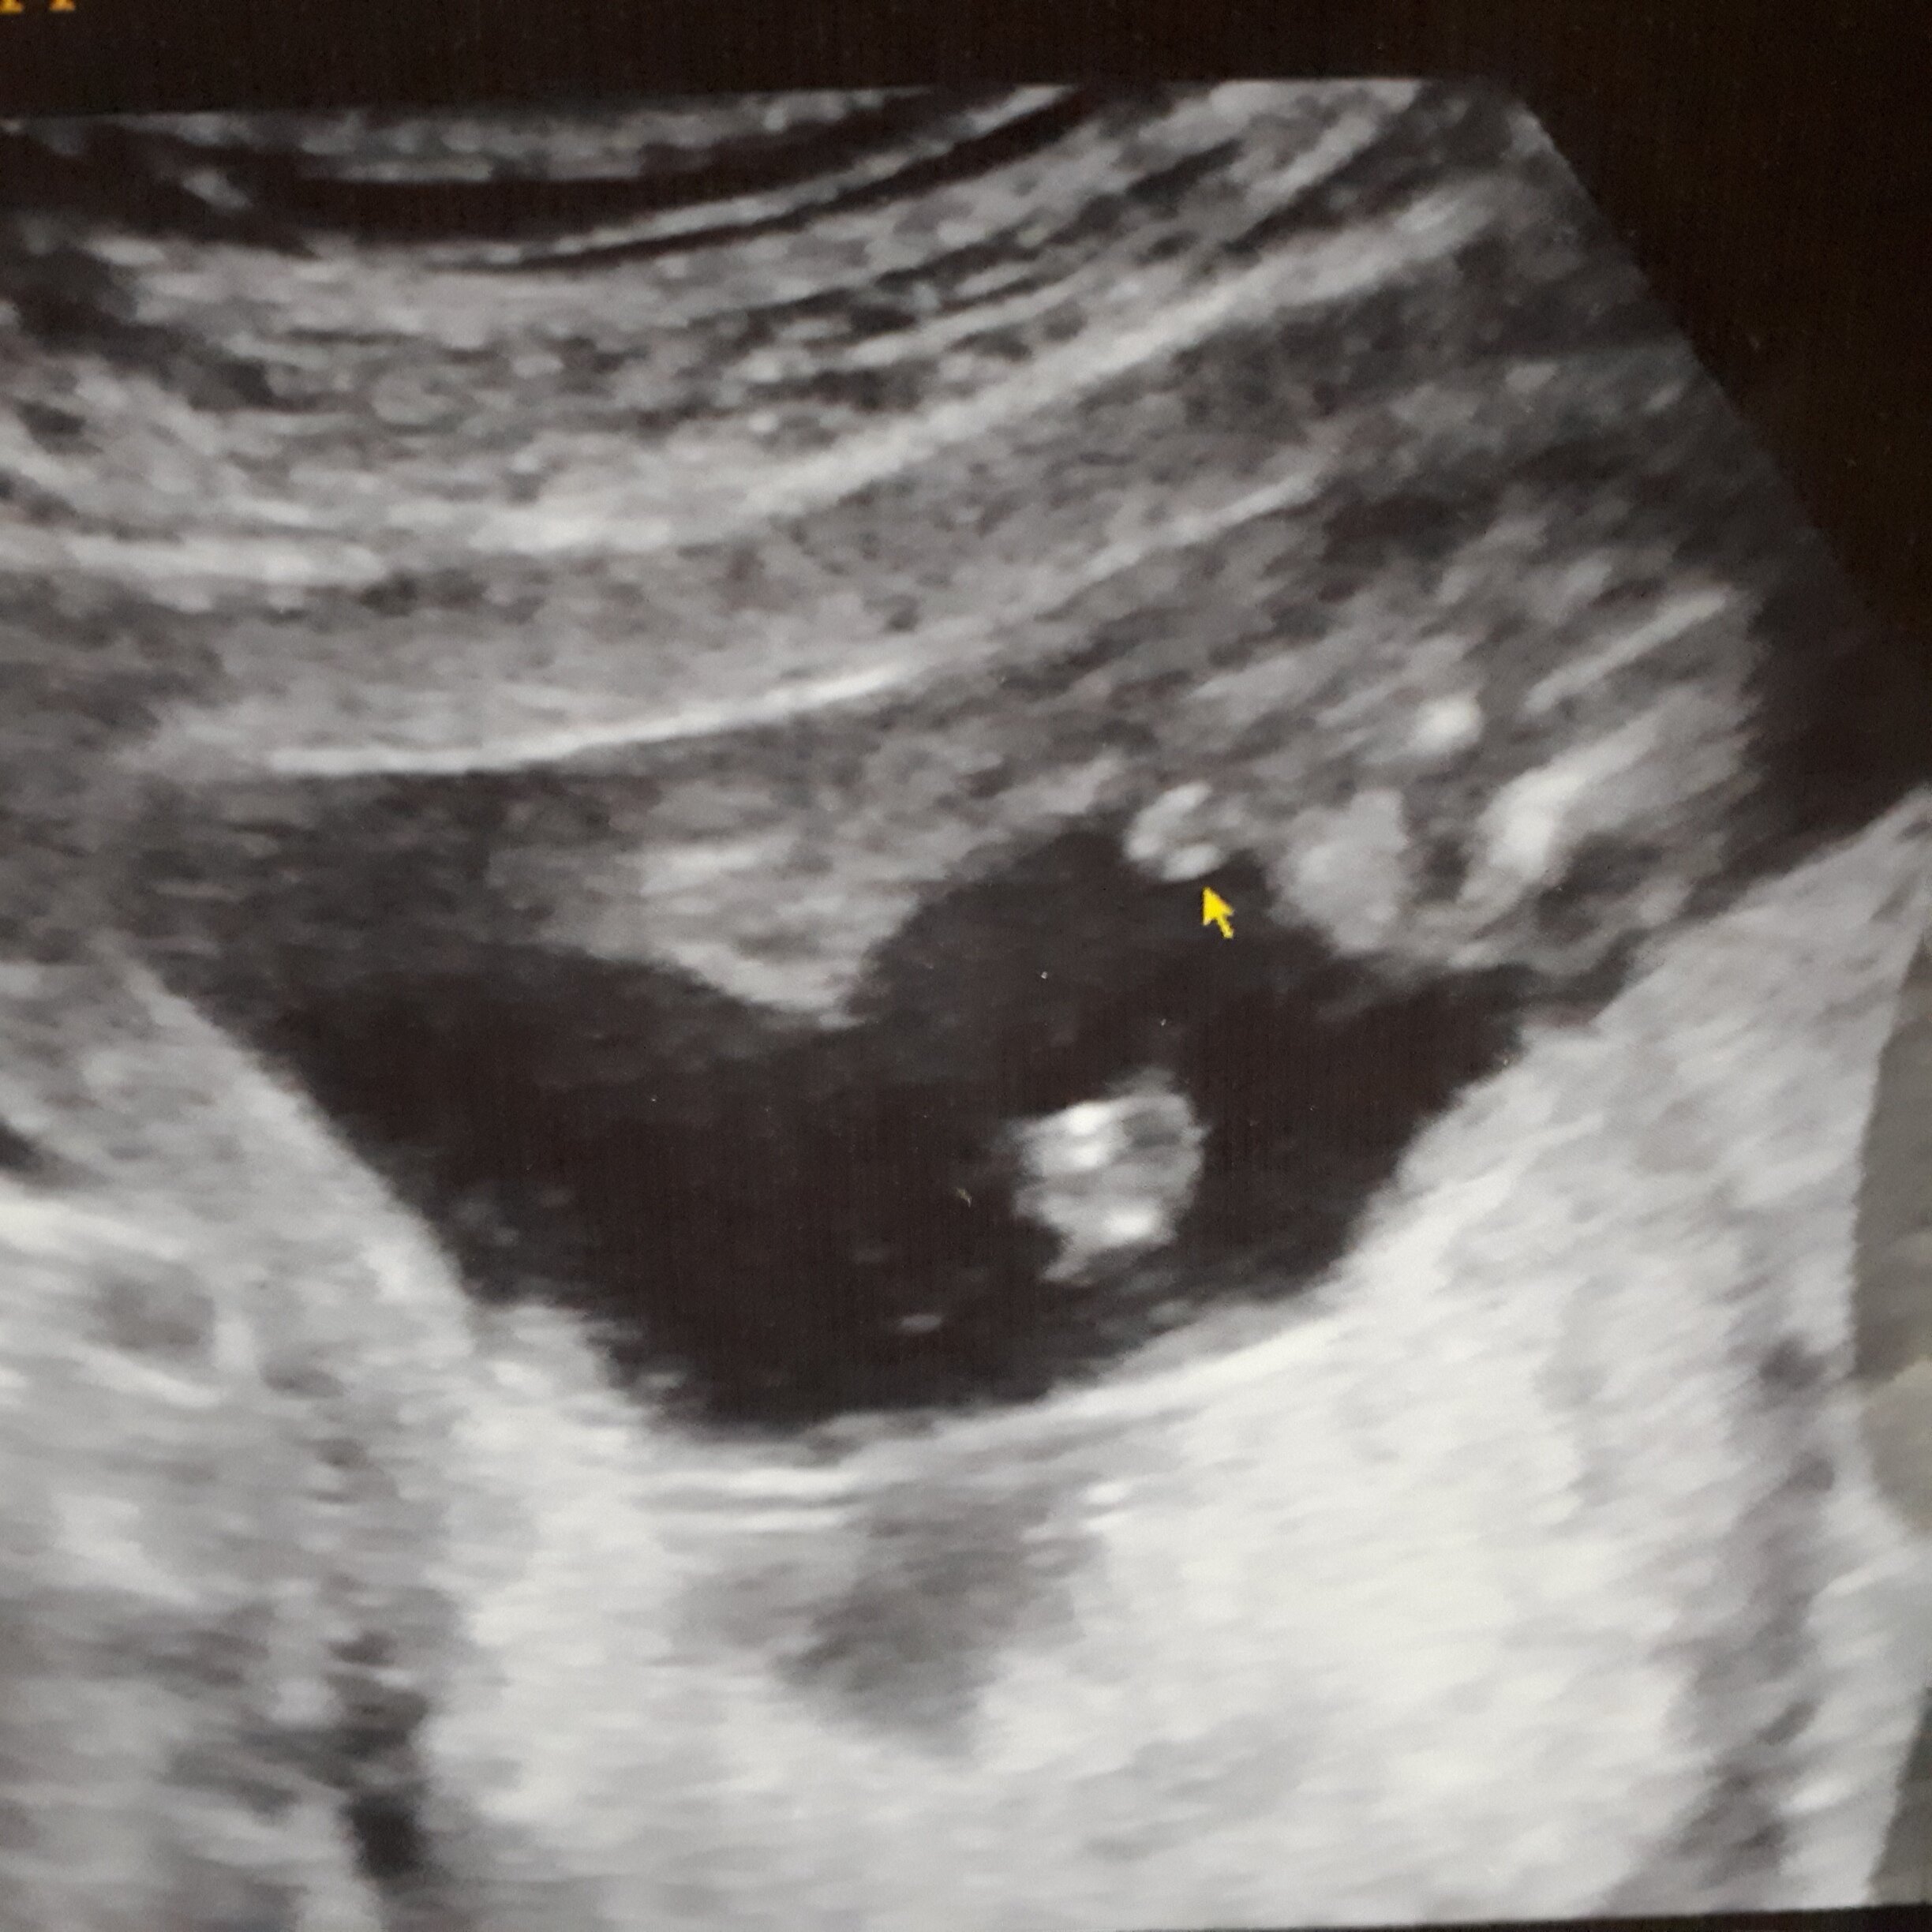

Jestem w 17 tygodniu.Tydzień temu poszliśmy z partnerem na usg żeby dowiedzieć się jaka jest płeć maluszka.Lekarz powiedział,że na ten moment przewiduje dziewczynkę, jednak to za wcześnie aby być pewnym w 100 procentach.Dlatego pytam was co uważacie.Pozdrawiam